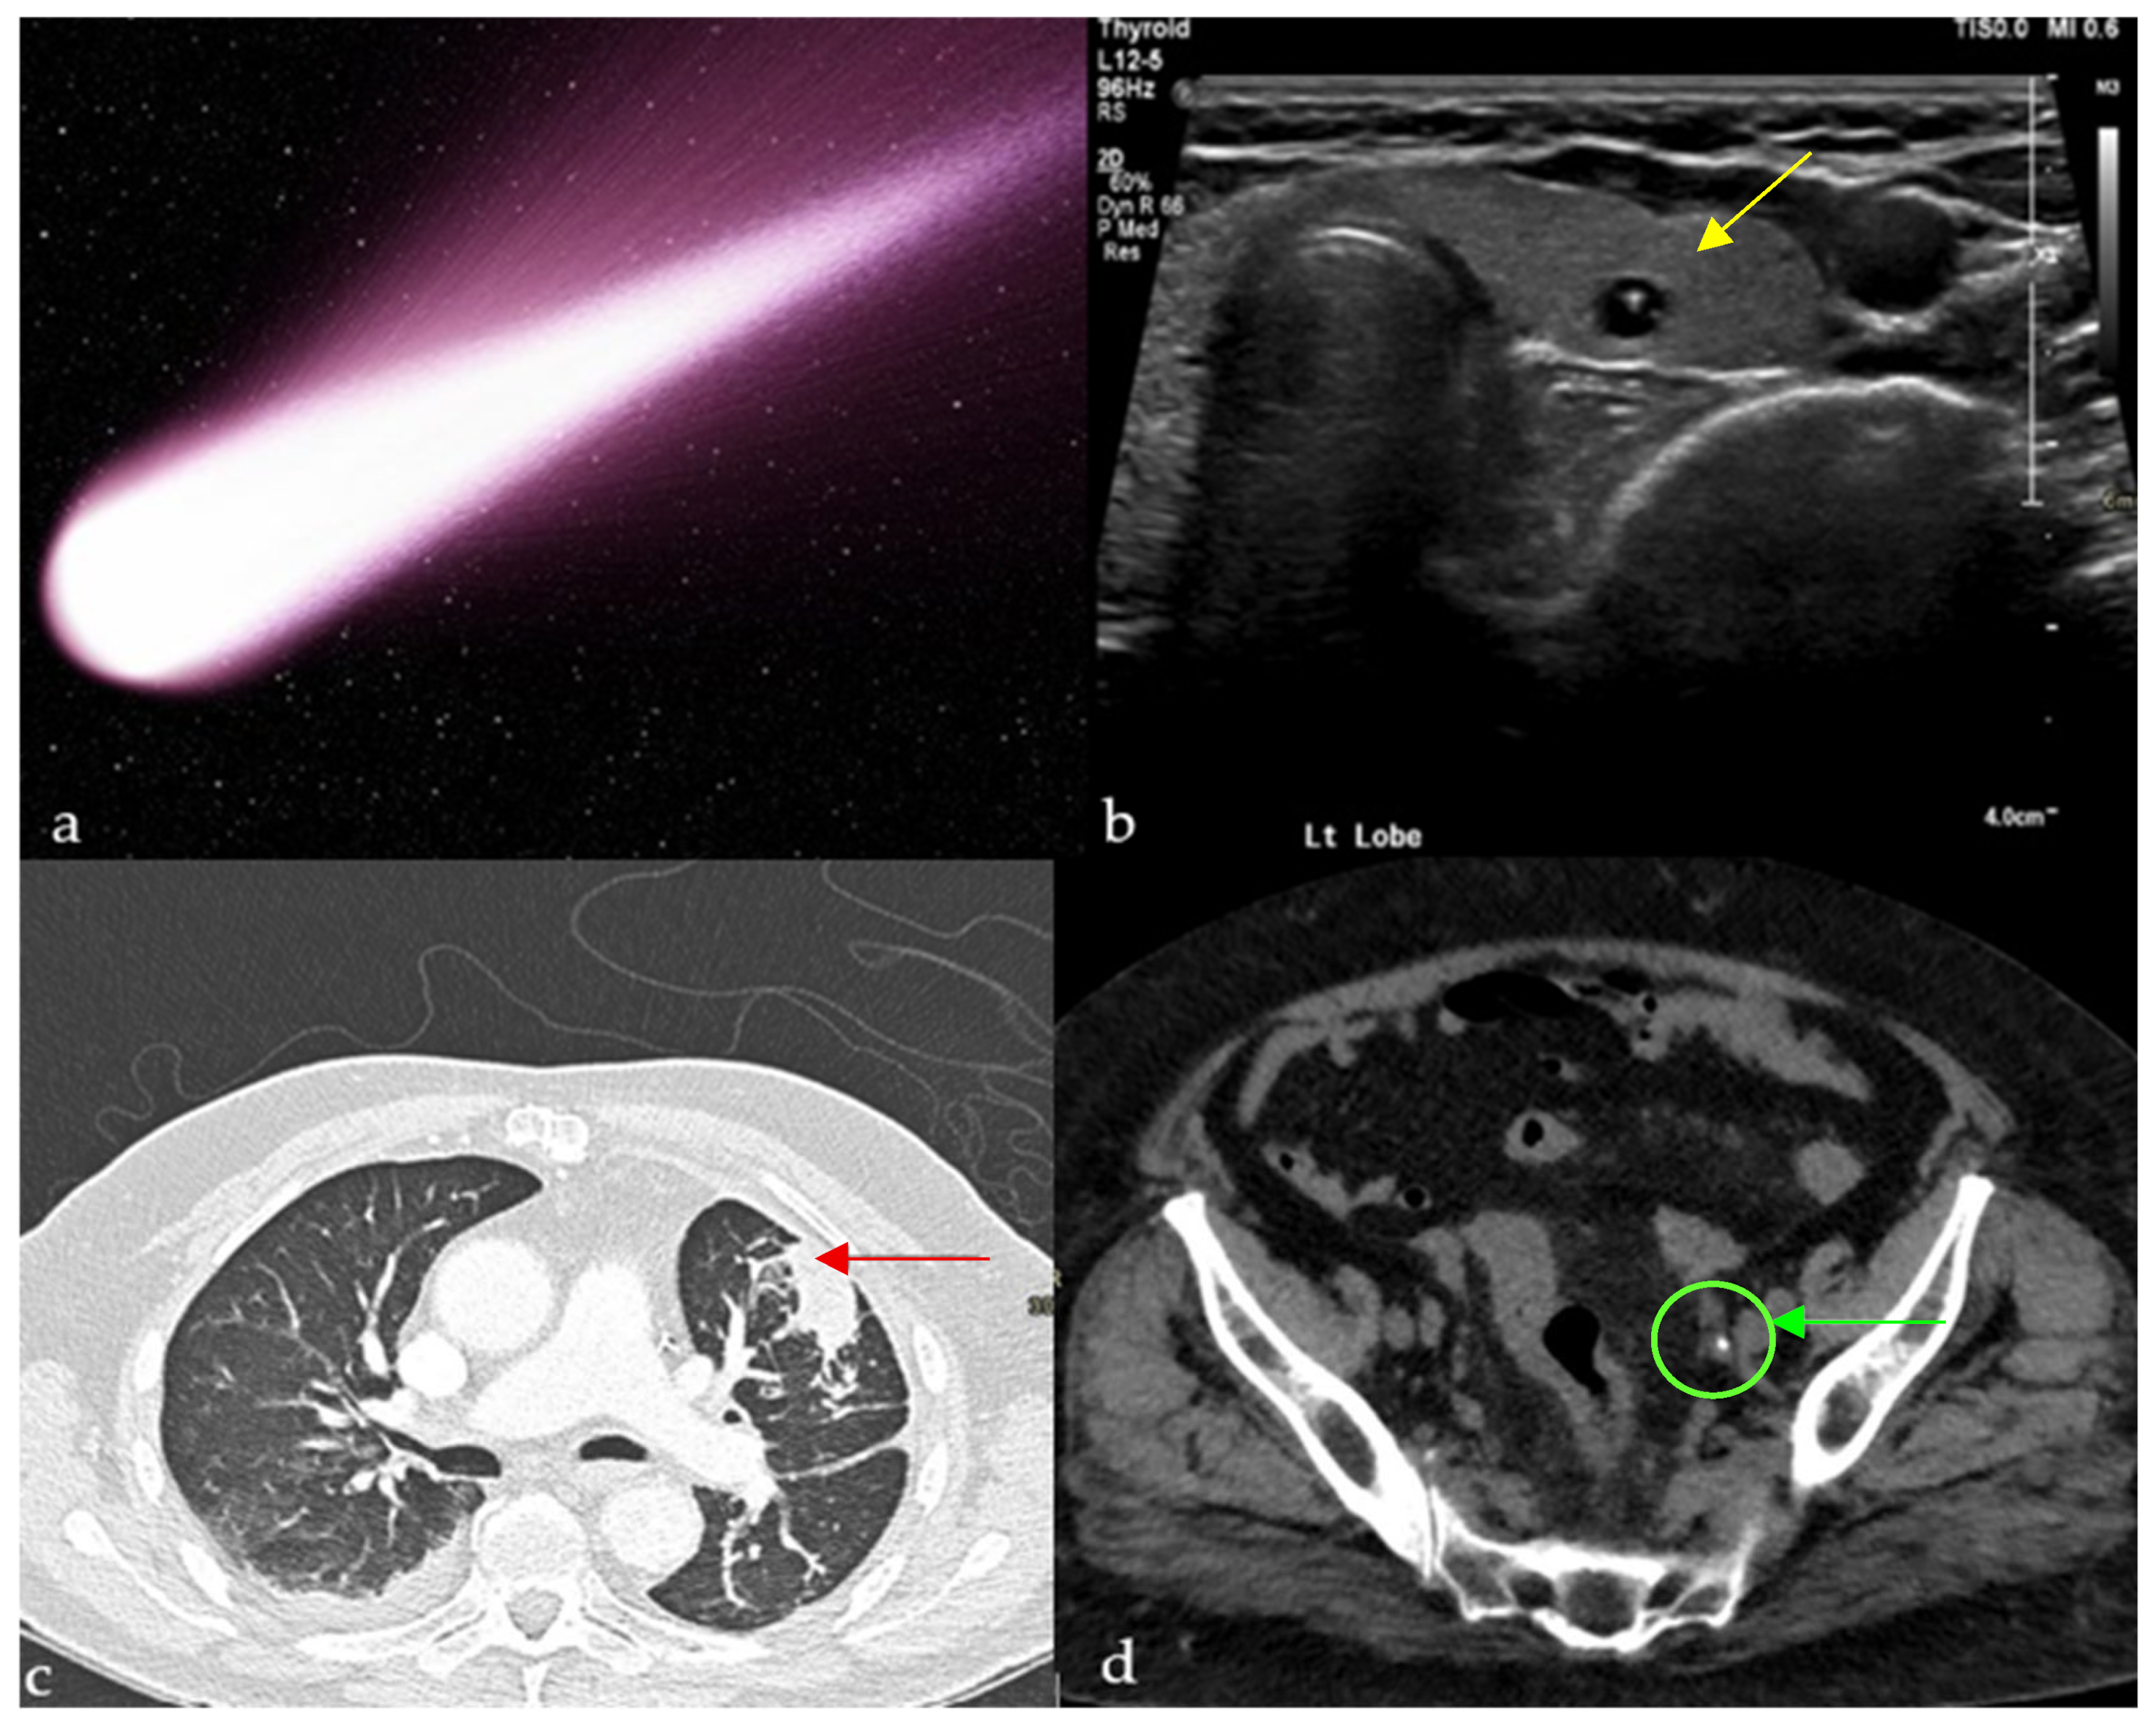

Similarly to a comet-tail (Figure 1a), this reverberation artifact appears as a sequence of parallel echogenic bands emanating from a definitive source [6]. It is attributed to reverberations from adjacent, highly reflective surfaces. Clinically, it clues into the diagnosis of multiple pathologies, such as adenomyomatosis of the gallbladder (due to cholesterol crystals within Rokitansky-Aschoff sinuses [7]) and colloid nodules in the thyroid (Figure 1b) [8]. It is a reassuring sign during focused assessment with sonography in trauma (FAST) examinations, since its appearance decreases the likelihood of a pneumothorax, with reported sensitivity and negative predictive value approaching 100%, albeit with a specificity of around 60% in differentiating from other interstitial processes [9,10]. This artifact is also present with calcifications and foreign bodies, such as clips and intrauterine devices [8].

Figure 1.

Small calcific/crystalline highly reflective structure causing reverberation artifact on ultrasound of the thyroid (yellow arrows) (b), axial CT of the chest showing a curvilinear opacity extending from a subpleural mass toward the ipsilateral hilum with distortion of vessels and bronchi (red arrow) (c), and tail of soft tissue extending from a calcification, representing the collapsed/scarred/thrombosed parent vein on a non-enhanced CT of the pelvis (green arrow) (d), all resembling a comet tail (a).

A recent case report describes comet-tail reverberation artifacts in the urinary bladder caused by cholesterolic debris in a patient with acute pancreatitis and Type V hyperlipidemia, highlighting that this artifact may also signal systemic lipid metabolism abnormalities beyond its classic associations with gallbladder adenomyomatosis or thyroid colloid nodules [11].

2.1.2. On Computed Tomography (CT)

Chest

This finding can be appreciated on both conventional chest radiographs and CT scans [12]. It represents round atelectasis (the comet’s nucleus), a benign form of pulmonary collapse adjacent to the pleural surface, which can mimic a malignancy, hence its other name, “pulmonary pseudotumor” [13]. This folding results in traction on the bronchovascular bundle, which leads to the typical curvilinear opacity originating from the mass and pointing towards the ipsilateral hilum (Figure 1c) [12]. As for the origin of these nodules, some attribute it to a local cleft in the visceral pleura resulting from an underlying effusion, others to a local process causing pleuritis, such as in the case of asbestosis [12]. Round atelectasis with the comet-tail sign is often associated with patients who have a history of chronic pleural disease, prior effusion, or asbestos exposure, and may present with cough, dyspnea, or pleuritic chest pain, though many cases remain asymptomatic and are discovered incidentally. Relying on radiological signs such as this one to differentiate this benign entity from malignancies is crucial because it saves patients unnecessary invasive procedures [13].

Abdomen and Pelvis

The clinical usefulness of this sign mainly lies in distinguishing a ureteric stone from a phlebolith, more notably in the anatomic pelvis [1]. The hyperdense calcified phlebolith is thought to resemble the body of the comet, whereas the remaining non-calcified vein would be the tail (Figure 1d). It is important to note that the combined secondary signs of obstructions (asymmetric stranding of perinephric fat, hydroureter, and hydronephrosis [14]) remain the clues with the highest positive predictive value to establish the presence of an obstructing stone [15]. In fact, studies showed the low reliability of the comet-tail sign in ruling out ureteric stones, with a sensitivity of 21–65% [16], and that in fact it might contribute to a missed diagnosis in some ambiguous cases [15]. Patients with acute flank pain may have calcifications in the pelvis; the comet-tail sign helps distinguish benign phleboliths from obstructing ureteral stones, guiding appropriate urologic management.